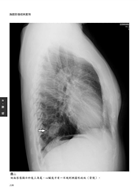

病例7 肝細胞癌(Hepatocellular carcinoma) 33